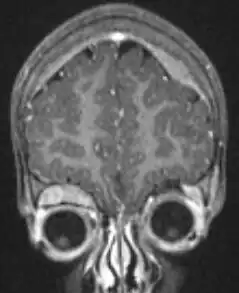

On microscopy, the tumor cells are typically described as small, round and blue, and rosette patterns (Homer Wright pseudorosettes) may be seen. Homer Wright pseudorosettes are tumor cells around the neuropil, not to be confused with a true rosettes, which are tumor cells around an empty lumen.[29] They are also distinct from the pseudorosettes of an ependymoma which consist of tumor cells with glial fibrillary acidic protein (GFAP)–positive processes tapering off toward a blood vessel (thus a combination of the two).[30] A variety of immunohistochemical stains are used by pathologists to distinguish neuroblastomas from histological mimics, such as rhabdomyosarcoma, Ewing's sarcoma, lymphoma and Wilms' tumor.[31]